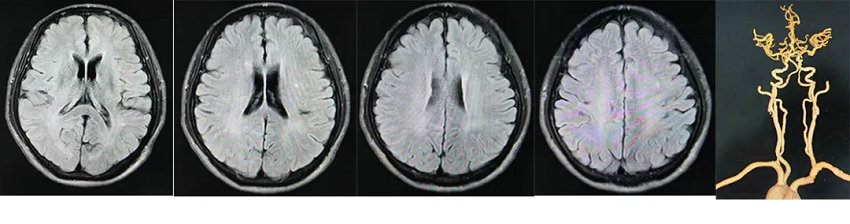

颅脑MRI平扫+DWI:

MRI未见新发梗死灶,左侧基底节区可见陈旧性腔隙性脑梗死,轻度脑白质脱髓鞘。

头颈联合CTA:

双侧颈内动脉多发混合斑及钙化斑,起始段管腔重度狭窄。

全麻下行全脑血管造影:

右侧颈内动脉起始段中度狭窄,狭窄率约为55%,左侧颈内动脉起始段重度狭窄,狭窄率约为90%。